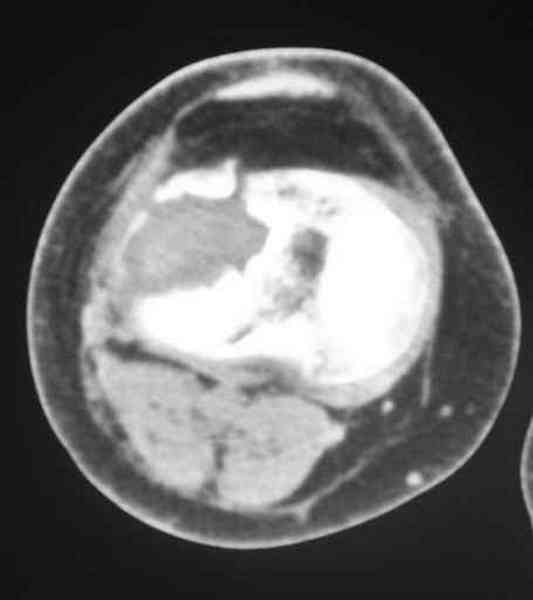

Обратился больной 46л. 3-месяца назад в каком-то городке Дальнего Востока упал с высоты, сделана Р-графия, наложена гипсовая повязка, от предложенной операции отказался и уехал домой, дальше где и как лечился, не говорит.

Ходит при помощи двух костылей, жалобы на боли при нагрузке, в покое и при движении, без нагрузке боли нет, разгибание 175 гр, сгибание 90 гр, симптомов повреждения связочного аппарата к/с не определяется, от предложенного артродеза пока отказывается.

По тактике лечения, более импонирует второй вариант, но наружная плато расколота и туда при нагрузке внедряется н/мышелка бедра, поэтому после дистракции как репонирвать: или стяжными винтами, или изогнутами спицами или субхондральная костная пластика?

Уважаемый Абдурашид. Если нет противопоказаний , то из оперативных способов, я бы рекомендовал следующие: Полное замещение наружного мыщелка аллотрансплантатом либо открытая репозиция с элевацией и замещение дефекта ауто или аллокостью. В Ваших условиях , я бы рекомендовал второй способ. Во-время элевации необходимо разъединить фрагменты со стороны сустава ( надсечь скальпелем по линиям перелома, а затем тонким остеотомом их разъединить. При помощи долота произвести неполную остеотомию ( захватите не менее 1,5 - 2 см губчатой кости и поднять фрагменты, визуально отрепонировать и фиксировать 2-3 спицами. Дефект заместить костным ауто или аллатрансплантатом. Окончательная стабилизация пластиной ( лучше с угловой стабильностью, либо АВФ - позволит спокойно устранить угловую деформацию.

У пациента основной проблемой является импрессионый перелом наружного мыщелка, уже неправильно сросшийся, по-видимому. Аппаратом закрыто можно только подправить угол на уровне метадиафиза. Что

улучшит разве что внешний вид конечности, но не решит основной проблемы - грубой деформации суставной поверхности.